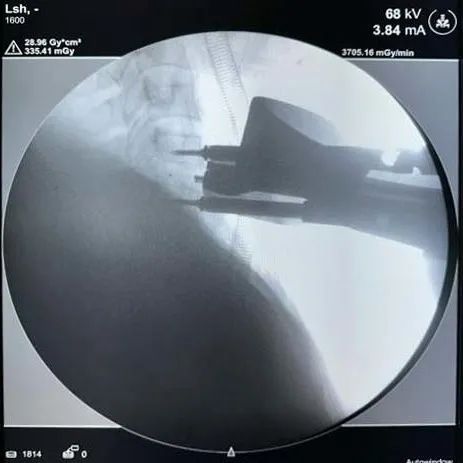

術(shù)中影像

融合器打入及確認(rèn)——

固定夾打入及確認(rèn)——